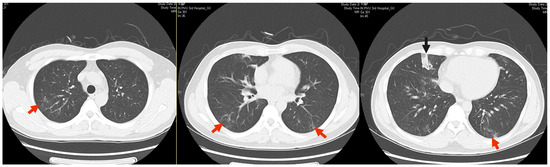

1. Case Presentation